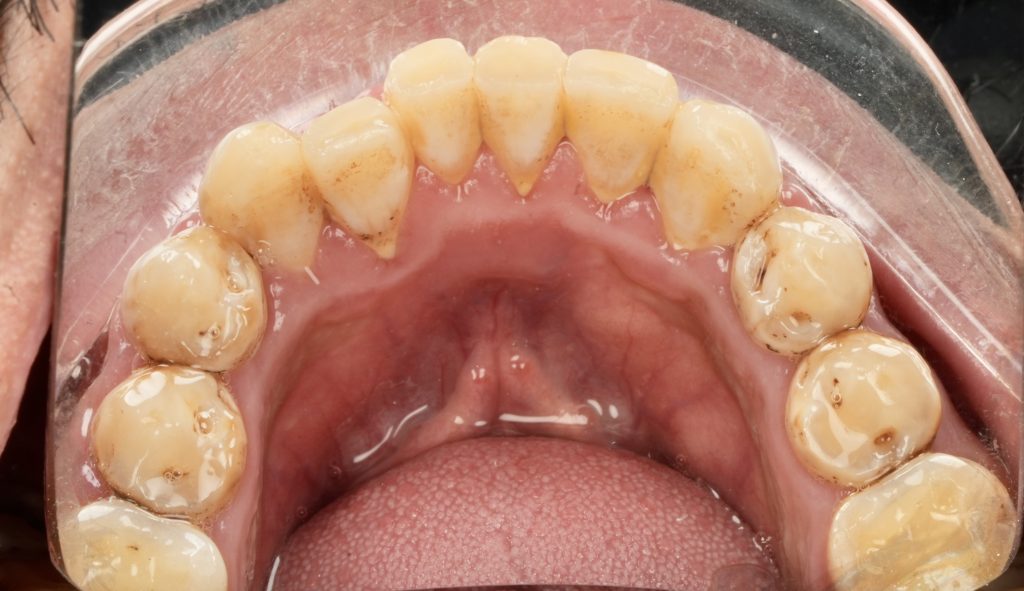

The patient sought esthetic improvement for uneven incisal edges, discolored anterior teeth, and disproportionate gingival display (Fig 1). A digital smile simulation and mock-up try-in were performed to assess tooth proportion, midline alignment, and incisal curvature. The plan prioritized enamel conservation and optical harmony.